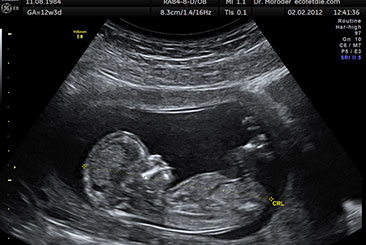

NT Scan

The NT scan (nuchal translucency) measures fluid at the back of the fetal neck to assess the risk of chromosomal abnormalities like Down syndrome.